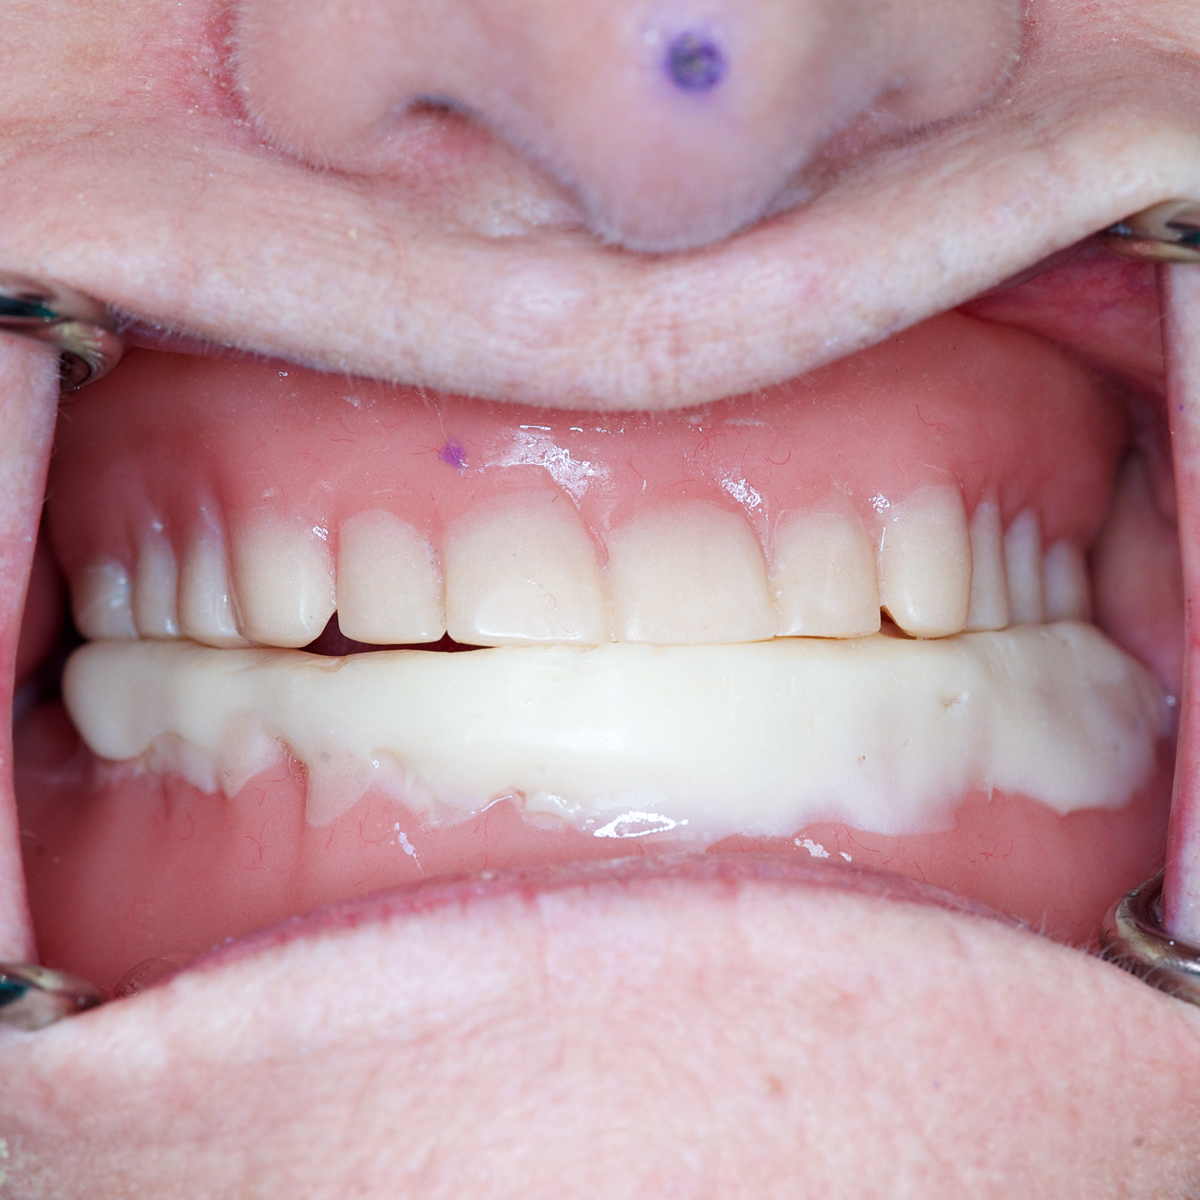

(3.) Gothic arch tracer assembly attached to the maxillary and mandibular dentures in preparation for fabrication of occlusal device.

Figure 3

(4.) Gothic arch tracer assembly attached to the maxillary and mandibular dentures in preparation for fabrication of occlusal device.

Figure 4

(5.) The maxillary and mandibular dentures with the attached intraoral tracer assembly are placed in the patient’s mouth, and the space between the maxillary posterior teeth and the mandibular posterior teeth is analyzed.

Figure 5